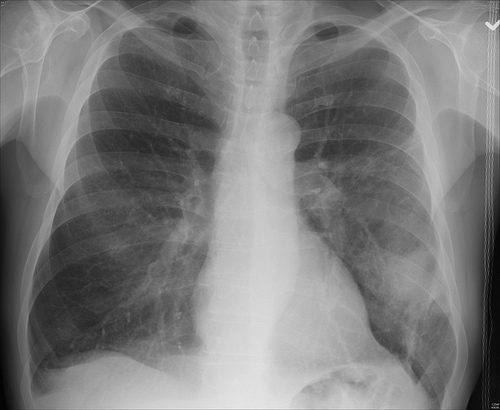

Día Internacional de la Lucha contra la Neumonía #FightPneumonia

Me llegó esta información sobre el Día Internacional de la Lucha contra la Neumonía #FightPneumonia . Las personas mas susceptibles a ella son los niños menores de 2 años y los adultos de más de 65 años. En el marco del Día Mundial de la Neumonía, especialistas recordaron los peligros que representa esta infección respiratoria,…